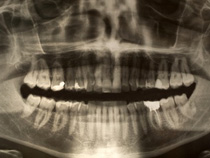

When X-rays pass through your mouth during a dental exam, more X-rays are absorbed by the denser parts (such as teeth and bone) than by soft tissues (such as cheeks and gums) before striking the film or x-ray sensor (in the case of digital x-rays). This creates an image on the radiograph. Teeth appear lighter because fewer X-rays penetrate to reach the film. Cavities and the resultant bone loss from gum disease appear as darker areas because of more X-ray penetration. The interpretation of these X-rays allows the dentist to safely and accurately detect hidden abnormalities.